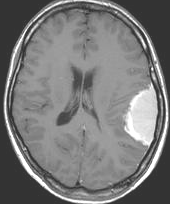

左は,造影剤を使ったガドリニウム増強MRIです。腫瘍が白く丸く見えます。右はフレア画像で,腫瘍の周囲の脳浮腫(脳のはれ)です。左前頭葉が,かなり強くはれています。この腫瘍は小さいのですが,脳のはれが強すぎるので手術摘出したほうがいいです。浮腫が悪化すると,てんかん発作や認知機能低下がでる可能性があります。

MRIでの髄膜腫の見え方は撮影の仕方によっていろいろです。左からT1強調画像,T2強調画像,フレア画像といいます。腫瘍の横に小さく白い領域がありますが,これは脳の腫れた部分で脳浮腫といいます。髄膜腫があると周囲に脳浮腫が生じることがあります。

最も見やすいのが,ガドリニウム造影剤を注射して撮影するものです。一般的に髄膜腫は造影剤で白く映し出されます。この腫瘍は左脳側にあります。MRIの軸面という輪切りの写真では左右が逆になりますから注意してください。脳を下から見た図になっています。MRIはいろいろな方向から腫瘍を見ることができますが,右は冠状断という正面から見た図です。よく見ると腫瘍の上と下のはじっこに線状に糸を引いたように造影される部分があります。これをテールサイン(しっぽのサイン)といいます。腫瘍が硬膜に沿って延びている可能性があることを示しています。